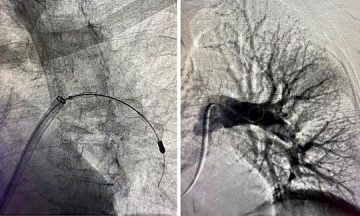

Die Weihnachtszeit ist für viele eine Zeit der Freude, doch bringt sie auch gewisse Gesundheitsrisiken mit sich. So ist die Gefahr für einen Herzinfarkt am Heiligen Abend im gesamten Jahr am höchsten, wie dänische Forscher*innen vor wenigen Jahren in einer Studie zeigten. Risikofaktoren wie Stress, fettes Essen und wenig Bewegung Weiterlesen…